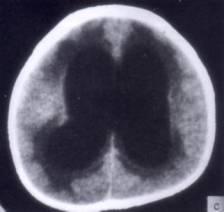

问题 病历摘要:??患者女性,10岁。结核性脑膜炎愈后8月,头痛伴恶心呕吐1周,并渐加重。体检:神清,精神差,反应迟钝,双眼底视神经乳头水肿,双眼外展差,余未见明显异常。 侧脑室-腹腔分流术后并发症包括下列哪些?

选项 A.分流管堵塞 B.分流过度 C.分流不足 D.硬膜下积液 E.感染 F.硬膜下血肿 G.癫痫

答案 ABCDEFG

解析 ABCDEFG